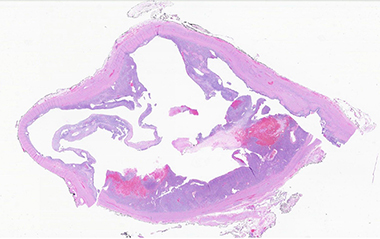

B. Complex cystic architecture (low power)